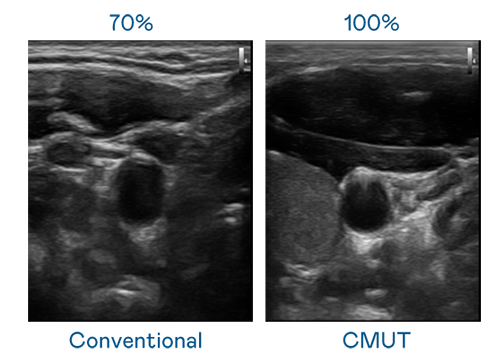

CMUT 技术是一种用电容式微机电元件来产生超音波讯号的技术。与传统 PZT 压电式技术相比,CMUT 频宽增加 30%,更宽频的超音波讯号让影像解析度大幅提升,是实现高影像品质医疗超音波扫描、促进精准医疗发展的关键技术。

大频宽带来超清晰影像

超音波影像的解析度高低,首先取决于探头能发出的讯号频宽。开云电竞 CMUT 可提供高清晰的超音波讯号,提供高频宽、高灵敏度、影像纹理细节更高的超音波影像,协助医护人员缩短影像判读时间及利用精准的医疗影像进行诊断。